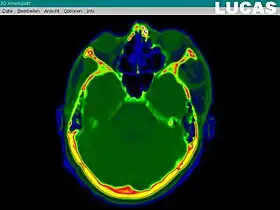

Data gathering, based on CT "slices" | |

Data from separate bidimensional slices generated by a CT or MRI scan are uploaded into the LUCAS system. The resulting dataset is then processed, in order to eliminate image noise, and to enhance the anatomical contours and also the general contrast of the images. The next step is to create a virtual 3D model from the gathered collection of 2D images. The bone segment that is to be repositioned is marked, on the 3D grid reconstructed model; then, the actual repositioning of that bone segment is done on the virtual model, until the optimal anatomical position is obtained. The criteria for the optimal position of the bone segment are: symmetry with the opposite side, the continuity of the normal bone contours, or the normal volume of an anatomical region (such as the Orbit. Afterwards, a textured final image is rendered. The calculated vectors for the bone segment repositioning, together with the whole virtual model are finally transferred to the Surgical Segment Navigator.